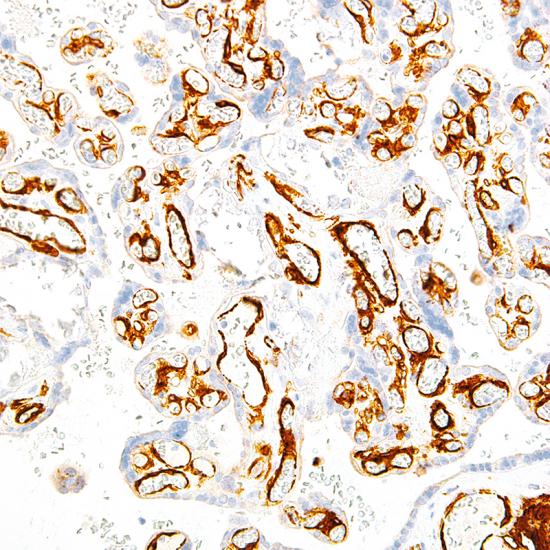

Flt-1/VEGFR1抗體試劑(免疫組織化學(xué)法) 閩廈械備20190173號

• 陽性部位:

細(xì)胞漿/細(xì)胞膜

• 陽性對照:

胎盤組織

參與內(nèi)皮細(xì)胞生長的有三種細(xì)胞膜受體酪氨酸激酶,分別是Flt-1(VEGFR1)、Flk-1(VEGFR2)和Flt-4(VEGFR3)。VEGFR1是一種參與淋巴管生成、血管生成和傷口愈合的酪氨酸激酶。它存在于內(nèi)皮細(xì)胞、成骨細(xì)胞、胎盤滋養(yǎng)層細(xì)胞、腎系膜細(xì)胞和一些造血干細(xì)胞中。VEGFR1抗體可用于喉癌和食管癌的鑒別診斷。